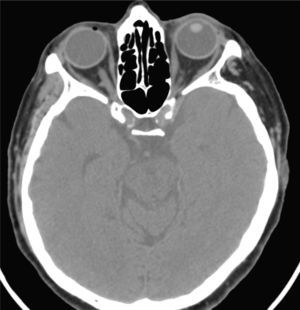

Mujer de 74 años, que consultó al servicio de urgencia por cuadro de cefalea occipital, luego de contusión craneana. Se le solicita tomografía computada de cerebro sin contraste (Figuras 1 y 2).

Figura 1